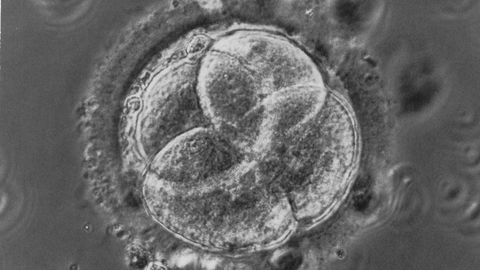

Las enfermedades hereditarias de base genética pueden corregirse en el embrión y evitar también que las mutaciones que causan la patología se transmitan a las futuras generaciones. Lo que aún parece ciencia-ficción está cada vez más cerca de convertirse en realidad. O cuando menos se ha demostrado que es posible. Es lo que acaba de probar un equipo internacional de científicos, con la participación del español Juan Carlos Izpisúa Belmonte, en una investigación publicada en Nature. Han logrado, por primera vez y mediante la herramienta de edición genética CRISPR-Cas9, corregir en embriones humanos la mutación que causa una alteración grave, la miocardia hipertrófica, una enfermedad hereditaria que afecta a una de cada 5.000 personas y que es la causa más común de muerte súbita en atletas. El hallazgo, aún en fases preliminares, abre también la puerta para la prevención de 10.000 trastornos genéticos que se transmiten de generación en generación.

Para sus experimentos, los científicos trabajaron in vitro con 142 embriones humanos en estados iniciales de desarrollo (oocito, blastocisto) y nunca los llegaron a implantar. En concreto, emplearon inicialmente 167 óvulos donados por mujeres sanas, de los cuales consiguieron fertilizar los 142 con el esperma de un solo donante: un hombre portador de una mutación heterocigótica en el gen MYBPC3, es decir, con una copia mutada dominante y otra correcta. De esta forma, sin ninguna intervención, se esperaría que un 50% de los ovocitos fecundados estuvieran libres de la mutación.